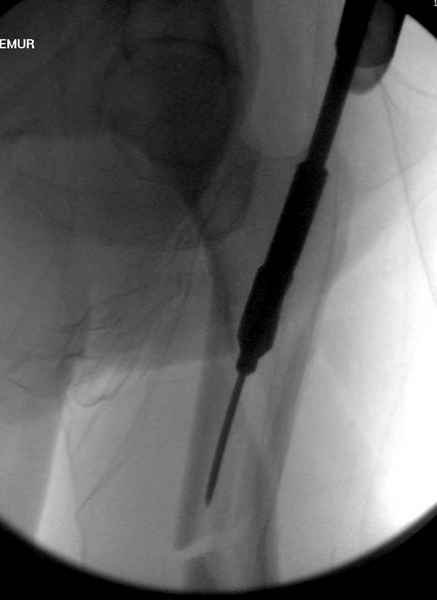

Среди русскоговорящих коллег Ортофорум стал одним из мест, где многие из нас черпают знания для решения своих ежедневных проблем в виде практических советов и обмена опытом. Кроме таких советов, Ортофорум стал источником новых познаний среди ортопедов, особенно по редко встречающимся состояниям в ортопедии. Продолжая традицию, я хотел бы представить редко встречающий случай перелома бедра у больного с гемофилией. Больному 42, гемофилия типа А, из истории упал с высоты около 1,5 метра, переправлен из другой больницы. По происхождению мексиканец, 10 лет назад по поводу артроза пр. коленного сустава в Мексике сделано протезирование, которое закончилось ампутацией выше коленного сустава. При поступлении бедро напряженное, сосудистых и неврологических расстройств нет. На рентгенограмме оскольчатый перелом бедра с вовлечением проксимальной спирали в шейку бедра. Хотели бы знать тактику ведения подобных больных и на что надо обратить внимание? Djoldas Kuldjanov, MD Department of Orthopedic Surgery St. Louis University Medical Center

Учитывая, что случай ургентный, больной поступил вечером, не стали делать вытяжение и срочно провели операцию по фиксации перелома бедра антеградным штифтом Versa Nail от DePuy.

Для профилактики дальнейшего раскола в шейке предварительно во время проксимального рассверливания спереди и сзади провели временные спицы, которые в дальнейшем были заменены на шурупы (miss nail method)